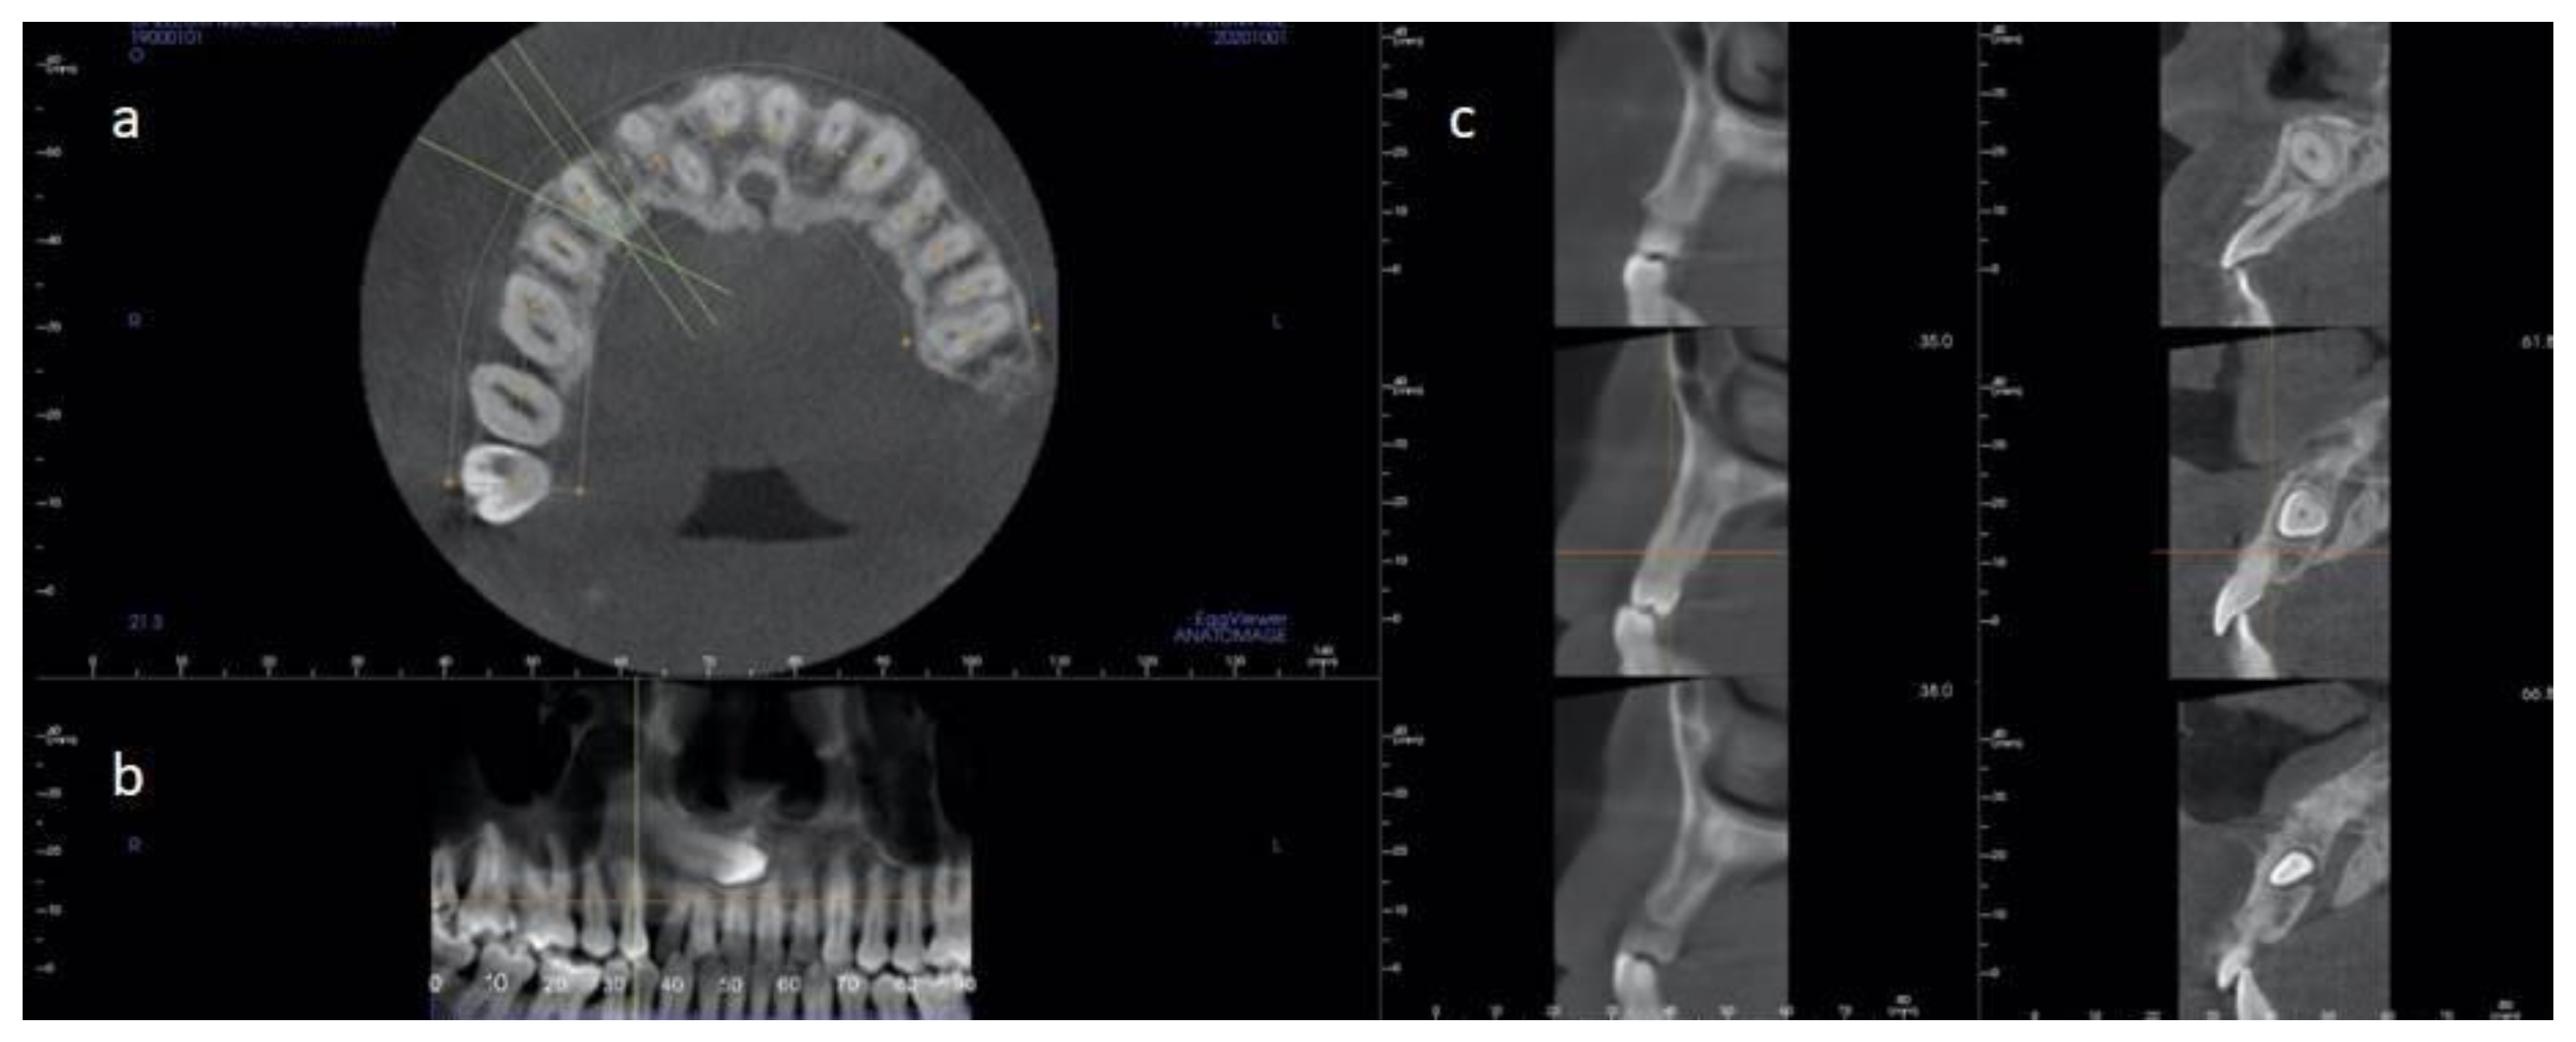

2.2.1. Case 1

2.2.2. Case 2